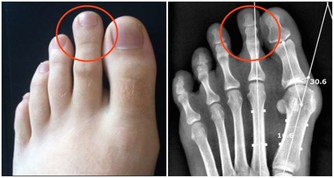

③出現便血要排查直腸癌需警惕痔瘡和直腸癌可能有存在一些類似的症狀,如便血。

但結直腸癌的便血和痔瘡的略有不同。

首先痔瘡可發生在任何人身上,而直腸癌的患者多為中老年人。

痔瘡患者的大便有血,是因排便時擦傷患處,不與糞便相混合更沒有黏液存在。

而直腸癌患者的大便則常混有血液、黏液和膿液等。